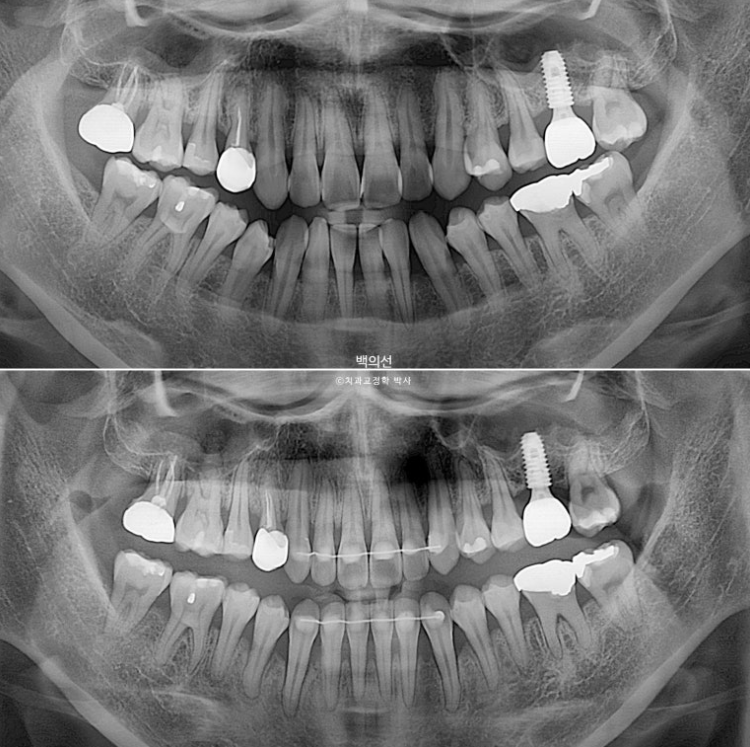

왼쪽 위 큰어금니 1개가 임플란트이며 앞니가 삐뚤삐뚤합니다.

1년 반의 치료기간동안 치근흡수는 없고 치근평행도는 좋습니다.

특히 아래 치열이 뒤로 움직이면서 사랑니 공간이 많이 줄어든게 보입니다.

윗입술은 전 후 변화가 없고 아래앞니가 뒤로 들어가면서 아랫입술이 따라 뒤로 들어가는 것이 보입니다.